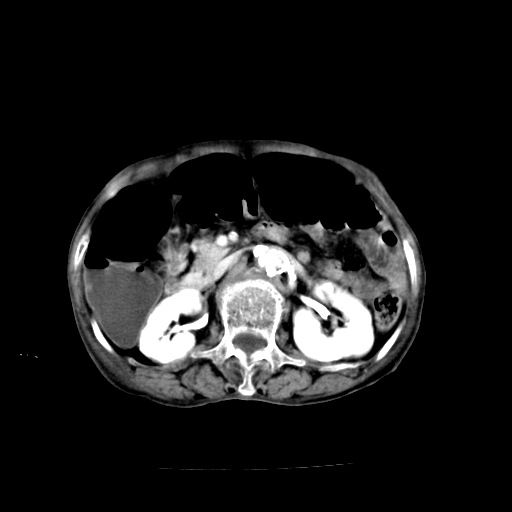

标题: CT19149:女,68岁,腹胀、恶心两周。 [打印本页]

女,68岁,腹胀、恶心两周,先做ct平扫,当时家属不同意强化,6天后家属要求增强扫描。

1)不排除胃窦癌;建议行胃镜检查。 2)局灶性脂肪肝。腹水。

考虑:胃窦ca,腹水,脂肪肝

支持考虑1、胃窦癌?建议行胃镜!; 2、局灶性脂肪肝。  3、双侧胸腔积液,胸膜增厚